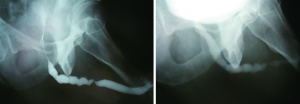

The sensitivity and specificity of RUG for the diagnosis of a urethral stricture has been reported in current literature. Sensitivities between 75% and 100% have been observed, with specificities of 72-97%. Typically, imaging is compared to cystoscopy and intraoperative measurements as a comparison. Positive predictive values have been reported from 50-93%, with negative predictive values varying in the 76-100% range (7-9). As such, retrograde urethrogram is considered to be strong in its ability to diagnose stricture, and further characterize its length, location, and number with a high degree of accuracy. Figure 3 demonstrates proper delineation of a long-segment penile urethral stricture related to lichen sclerosus which was initially assessed as a “meatal stenosis”. A long-segment (5 cm) idiopathic bulbar urethral stricture is demonstrated in Figure 4.